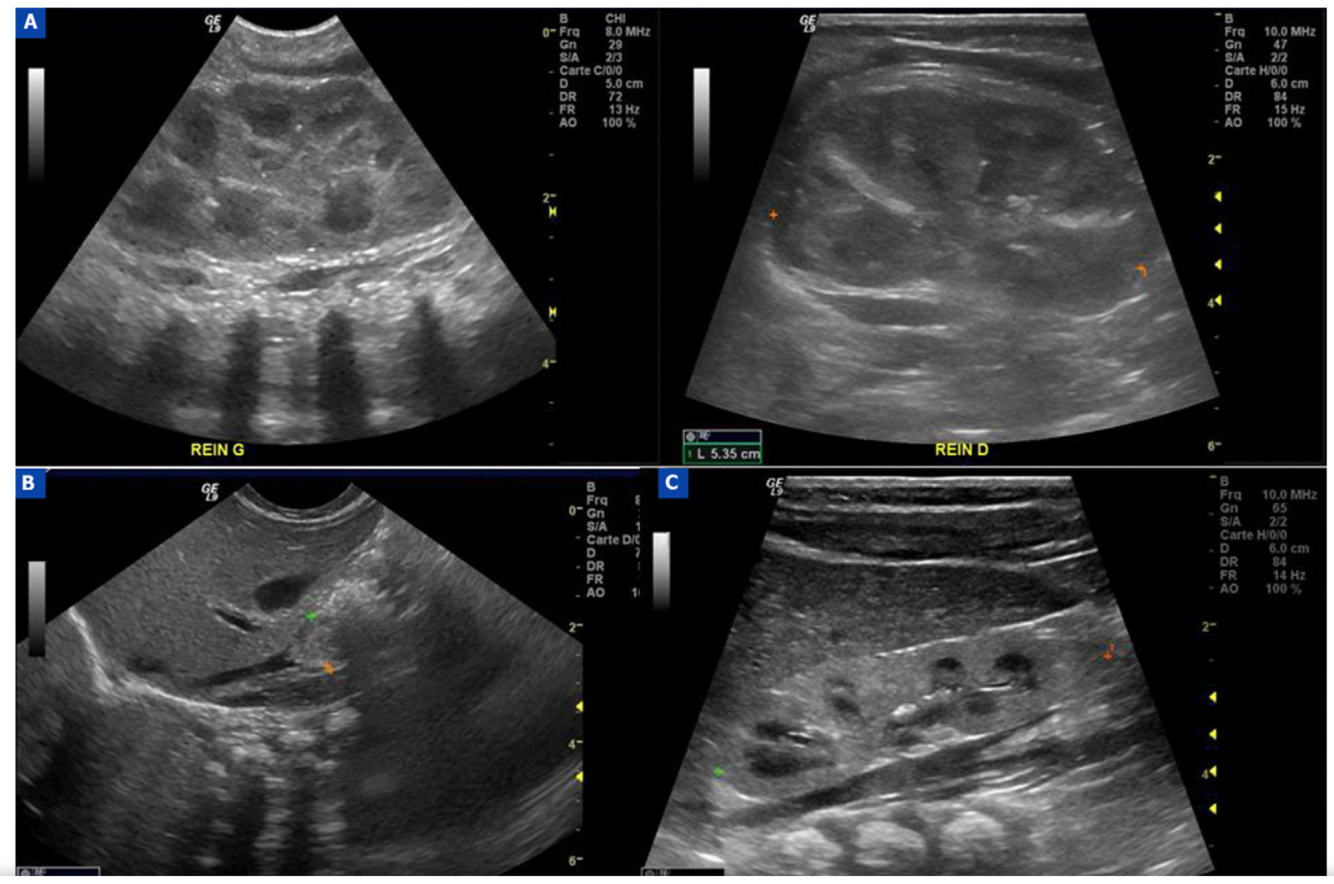

Imaging Features of Calyceal Diverticulum